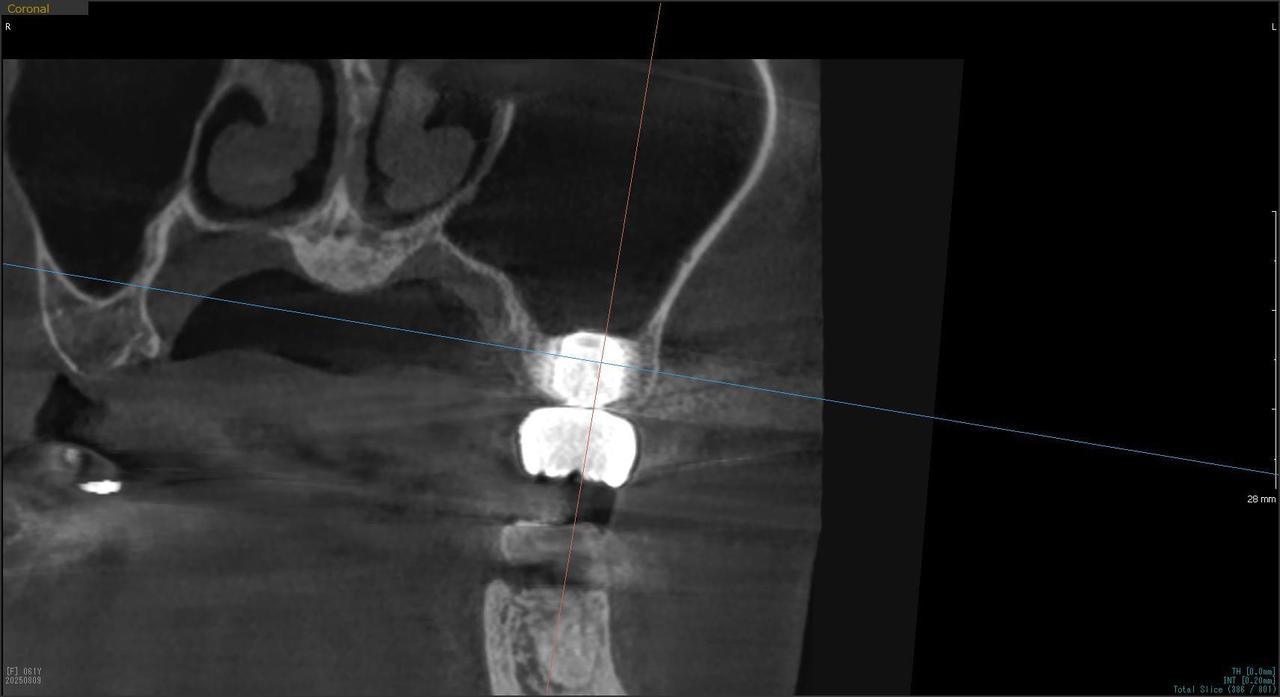

5.右上6番の歯根が破折したに大きな骨欠損を生じたケースに対して、通常なら、大幅な増骨手術(GBRとサイナスリフト)が必要で、最低1年は、かかるケースを、骨補填材なしで、インプラント埋入後、2.5か月で治療を終えたケース

Before

枚方市のインプラントの症例

H・M様 女性 60代

症状としては、左上6番の歯根が歯根が破折したために、炎症が起き、上顎洞底までの及ぶ大きな骨欠損がおきていた、

治療法としては、動揺がひどくなってきて、炎症の症状もあったため、抜歯を希望。抜歯後にインプラント治療を希望したために、CTを撮影したところ、かなりの骨欠損が生じていた。インプラントは不可能か大幅な増骨手術が必要なるようなケースであったが、ご自分の骨が少し残っていた部分にエクストラワイドインプラントで固定をとることと、グラフトレスサイナスリフトを併用する計画を立て、インプラント埋入術を施行。2か月後、インプラントがデータ測定上安定したために、光学印象で印象を行い、2か月半後に上部としてジルコニアクラウンを装着して治療を終えています。

治療結果として、大幅な骨欠損があったが、2か月半という短時間で治療を終えることができた。通常のサイナスリフト等の大幅な増骨手術を行った場合、患者様に、肉体的、金銭的、時間的な負担をかけることになったが、グラフトレスサイナスリフトとエクストラワイドインプラントを使用することにより、そのことを避けることができた。

治療の期間・回数:治療回数インプラント埋入後6回

治療の価格:363000円(税込)

治療費の内訳:インプラント基本料(フィックスチャー(メガジェンインプラントANYONE) 及び手術費用、投薬費用、レントゲン費用、インプラント上部費用(アバットメントおよびジルコニアクラウンの費用用)330000円(税込み)左上6グラフトレスサイナスリフト費用 33000円(税込)

治療のリスクや副作用:手術後に、痛みや腫れ、出血、合併症などを引き起こす可能性があります。噛む感覚がご自身の歯と異なる場合があります。見た目がご自身の歯と異なる場合があります。手術後にメインテナンスを継続しないと、インプラントが抜け落ちる可能性があります。